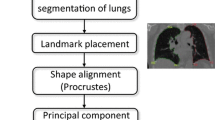

Subjects’ lung segmentation

Five lung segmentation methods were tested in 44 scans from 11 subjects (Fig. E2): one fully manual (ITK-SNAP) [23], two semi-automated (3D Slicer [24] and GeoS [25]), and two fully automated (Ivanovska [26] and Pennati [27]). Each segmentation method is explained in the Supplementary material.